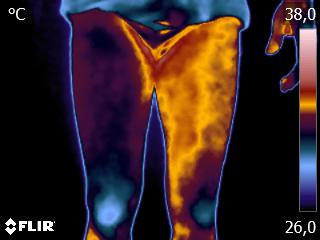

Caros colegas fisioterapeutas e terapeutas ocupacionais, vocês sabiam que, por meio do estudo da Termofuncional, é possível identificar alterações térmicas […]

Caros colegas fisioterapeutas e terapeutas ocupacionais, vocês sabiam que, com o estudo da técnica Termofuncional, é possível identificar alterações térmicas […]